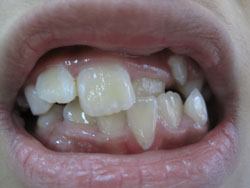

- *Răng mọc chen chúc:

- Răng mọc chen chúc là tình trạng các răng sắp xếp lộn xộn, không ngay ngắn trên cung hàm , răng mọc không đều, các răng khấp khểnh do thiếu chỗ (răng quá to hay xương hàm cung răng quá nhỏ không đủ chỗ để các răng sắp xếp).